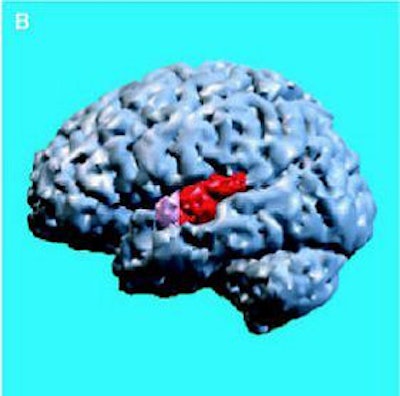

| Same subject. Above and below, axial MRI is used to present top-down views of the 3D reconstruction of the amygdala-hippocampal complex and parahippocampal gyrus. All images: Figure 1, Hirayasu Y, Shenton ME, Salisbury DF, et al. "Lower Left Temporal Lobe MRI Volumes in Patients with First-Episode Schizophrenia Compared with Psychotic Patients With First-Episode Affective Disorder and Normal Subjects," (Am J Psychiatry 1998; 155:1384-1391). |